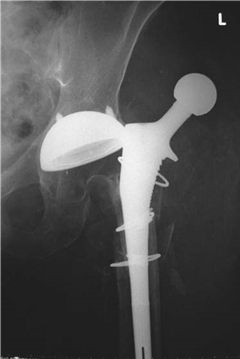

What condition is illustrated here?

Avascular necrosis of the femoral head with segmental collapse.

Can you describe any classifi cation systems for this condition? What stage is shown in the radiographs above?

There are many classifi cation systems described for osteonecrosis of the hip. The Ficat and Arlet (1980) system describes X-ray appearances and is one of the most simple to use:

Stage 1: no bony changes seen on plain X-ray

Stage 2: sclerotic and cystic changes within the femoral head

Stage 3: subchondral collapse and distortion of the femoral head

Stage 4: secondary osteoarthritis with decreased joint space and articular collapse

T he radiographs show Ficat and Arlet stage 4 changes. There is distortion and collapse of the femoral head. The lateral view illustrates the โ€˜crescent signโ€™ associated with subchondral collapse.